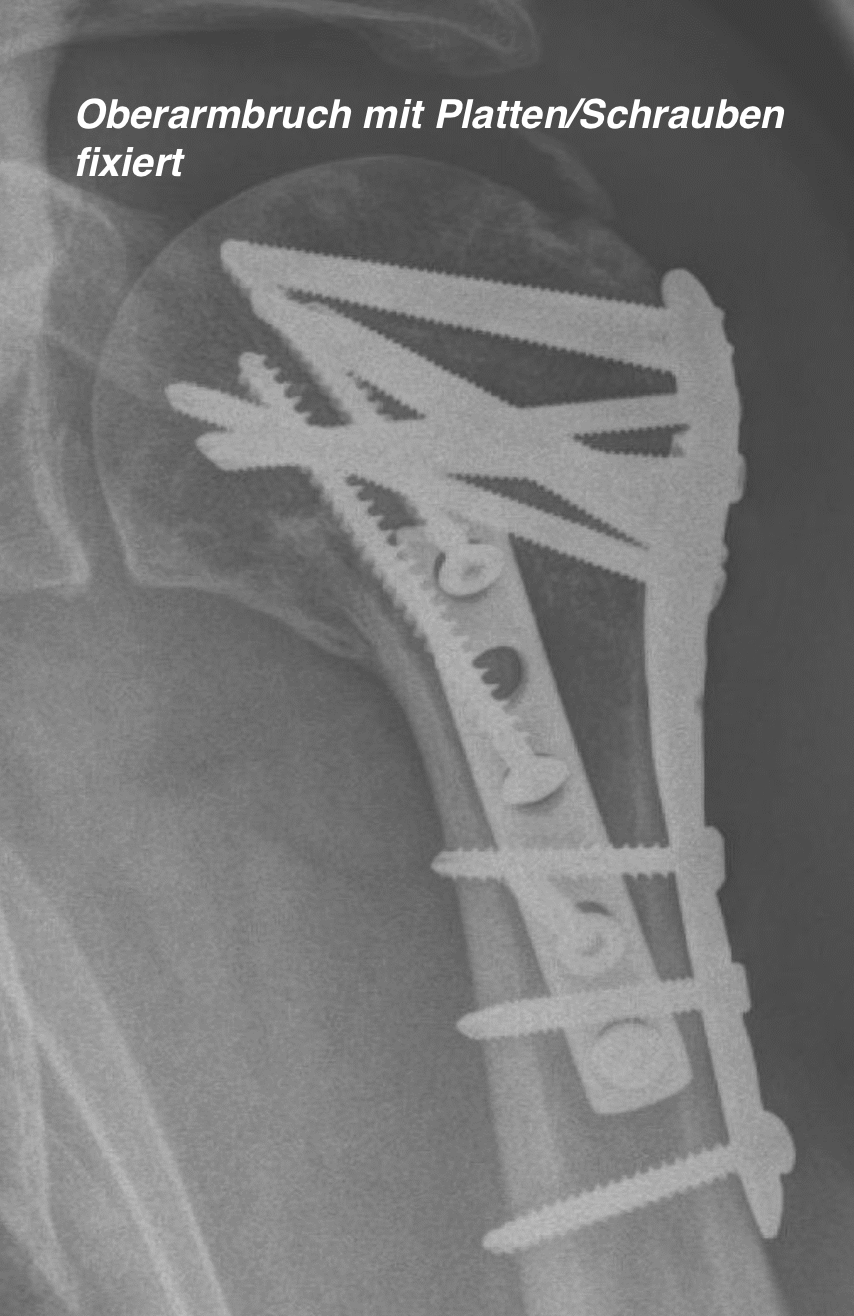

The treatment of shoulder fractures requires precise diagnostics and individually tailored therapy. In many cases - especially with stable, non-displaced fractures - conservative treatment with immobilization and subsequent physiotherapy may be sufficient. In the case of more complex fractures, displacements or joint involvement, surgery is often necessary to restore anatomy and function. In these cases, the fracture is repositioned (reduced) and fixed with plates and screws.

Today, modern surgical procedures allow for gentle treatment with plates, screws or - in the case of very serious complications - a joint replacement. The aim is always to restore mobility and weight-bearing capacity to the shoulder as quickly and safely as possible.